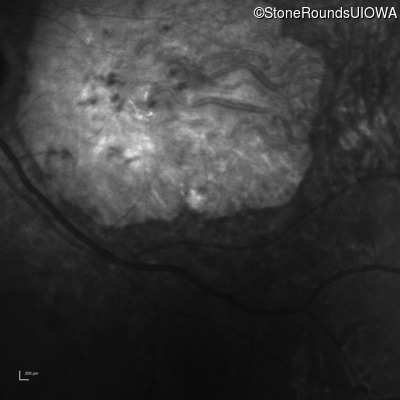

Infrared Fundus Photograph - Right - 20/160 +2 sc

Exemplar